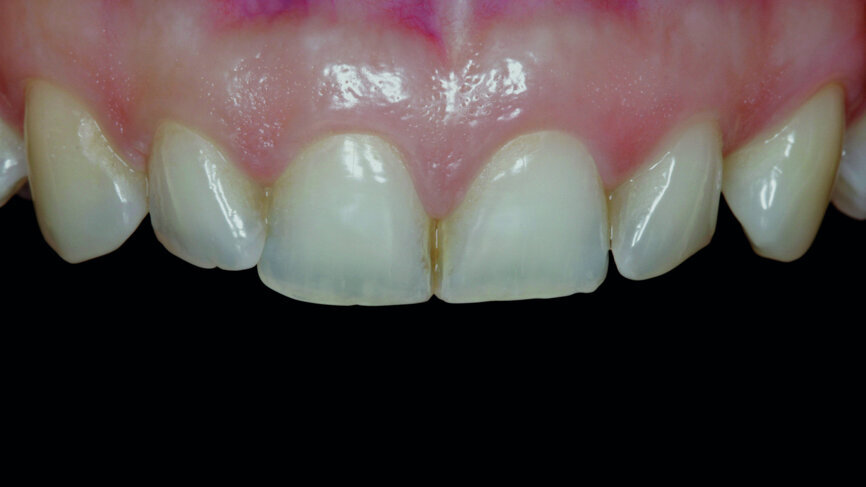

Fig. 2a: Anterior teeth after orthodontic treatment.

A 35-year-old patient presented at the office with the chief desire that the aesthetics in the anterior region be changed (Fig. 1). A diagnostic wax-up was performed, followed by mock-up fabrication, in order to obtain a preliminary visualisation of the final outcome. Orthodontic treatment was proposed in order to align the teeth in a more favourable position for veneers requiring minimal preparation and to reduce the overbite. One year after treatment, the patient returned for the final prosthetic rehabilitation (Figs. 2a & b).